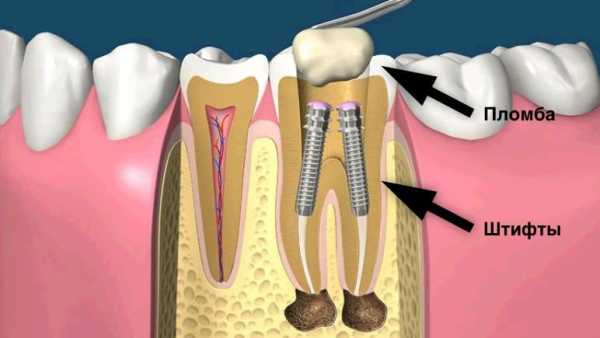

Для восстановления и исправления зубов сегодня разработаны десятки методов, каждый из которых призван быстро и безболезненно решать определенную клиническую задачу. При кариозных разрушениях лучше всего себя зарекомендовали вкладки, а при отсутствии у зуба опоры на помощь приходят штифты. Установка штифта при зубном протезировании осуществляется следующим образом: один конец стержня вкручивают в корневой канал, на другом крепят новый красивый зуб.

Штифтом стоматологи называют особый стержень с резьбой. С ее помощью один конец штифта вкручивается в корень зуба, на второй конец конструкции устанавливается протез. Штифтовый метод наращивания зубов актуален в тех случаях, когда верхняя часть зуба сильно разрушена, а корневые каналы в нормальном состоянии.

Установленный штифт

Порядок установки штифта